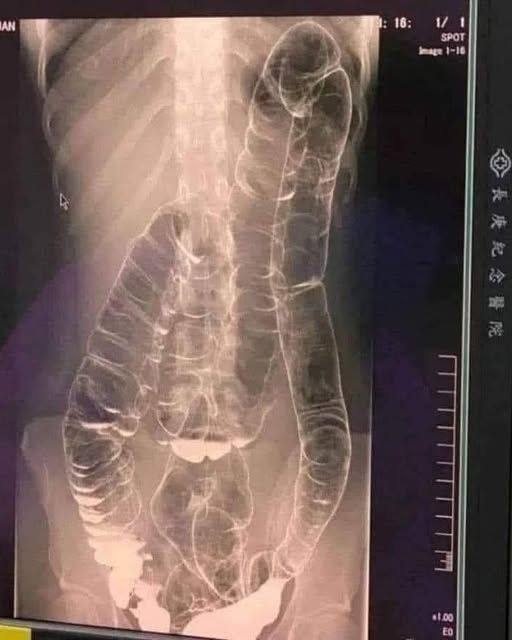

Constipation is a common digestive issue that affects millions of people worldwide. While it is often considered a minor inconvenience, prolonged or untreated constipation can lead to serious health concerns, including a rare but life-threatening condition known as toxic megacolon. This article explores the underlying causes, symptoms, complications, and effective lifestyle changes to manage and prevent chronic constipation in a safe and sustainable manner.

Constipation is typically defined as having fewer than three bowel movements per week. However, it is not just the frequency that matters—constipation can also involve difficulty passing stools, hard or dry stools, and a sensation of incomplete evacuation. It may be short-term (acute) or persist for weeks or longer (chronic).